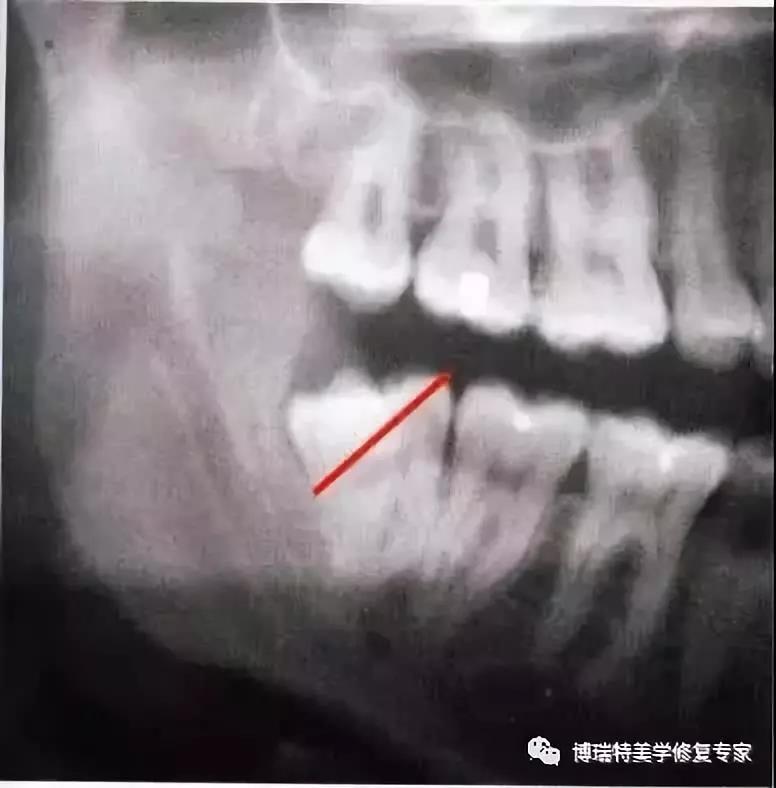

1、下颌第三磨牙阻生。代表牙槽窝深度的红线表明从牙槽嵴顶到釉牙骨质界间在近中颊角方向上的距离。考虑到患者的年龄,阻生牙牙槽窝的近中骨壁较容易以第二磨牙牙根旁的硬骨板为基础分化再生。因此,该患者第二磨牙牙槽骨修复重建的预后较好。